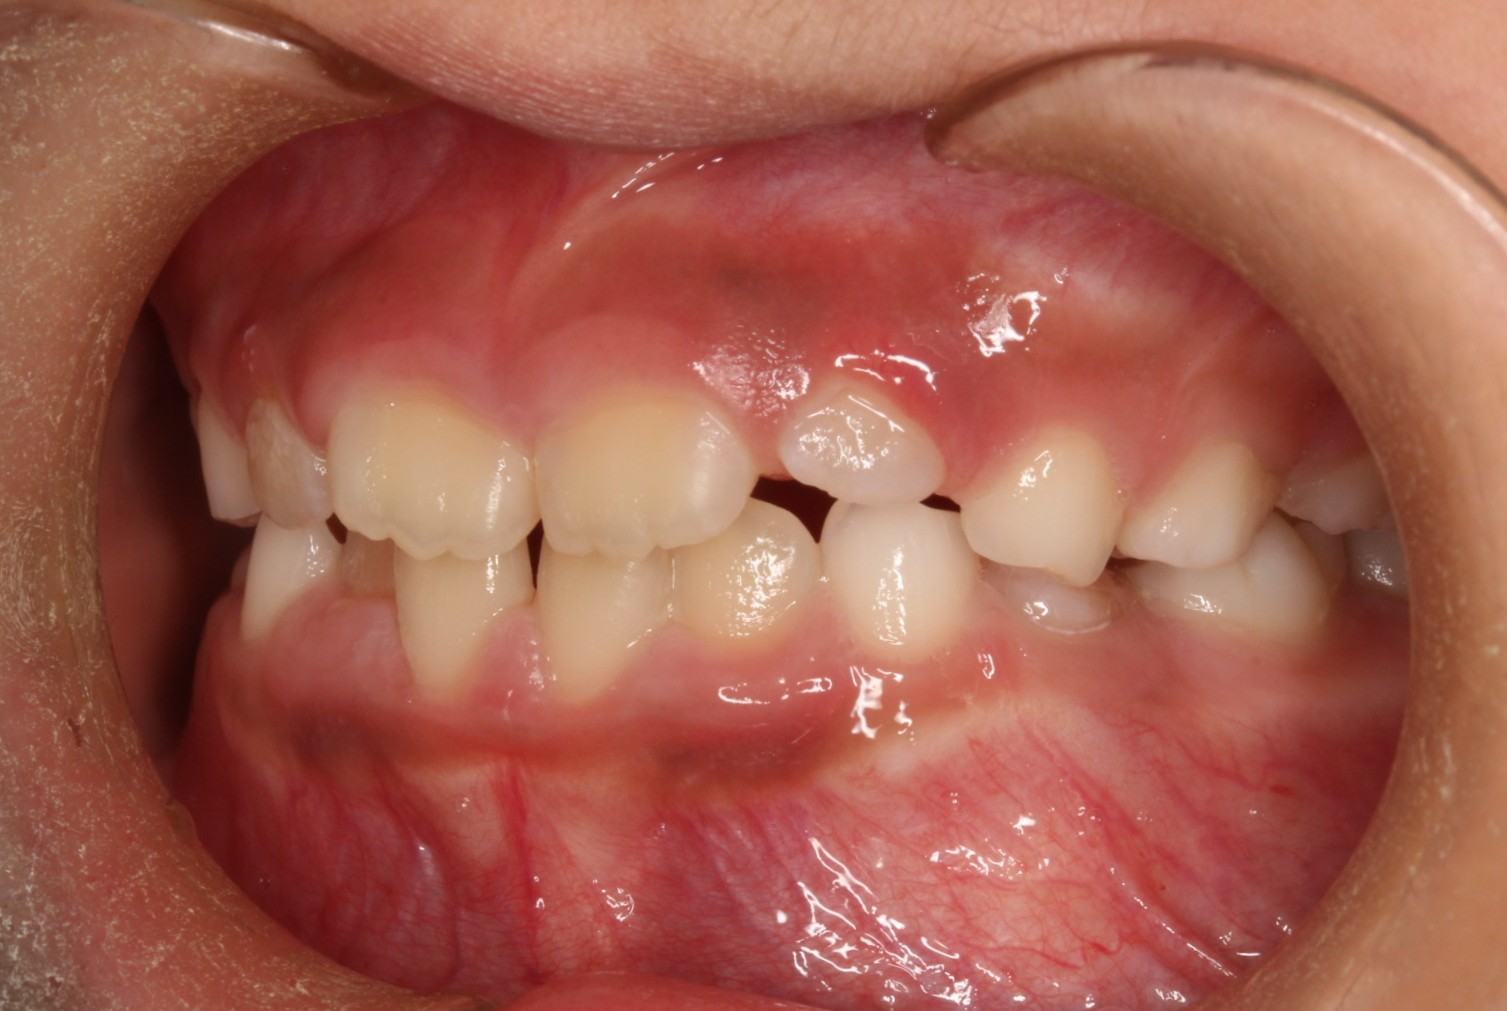

矯正術前:右側

矯正術前:左側